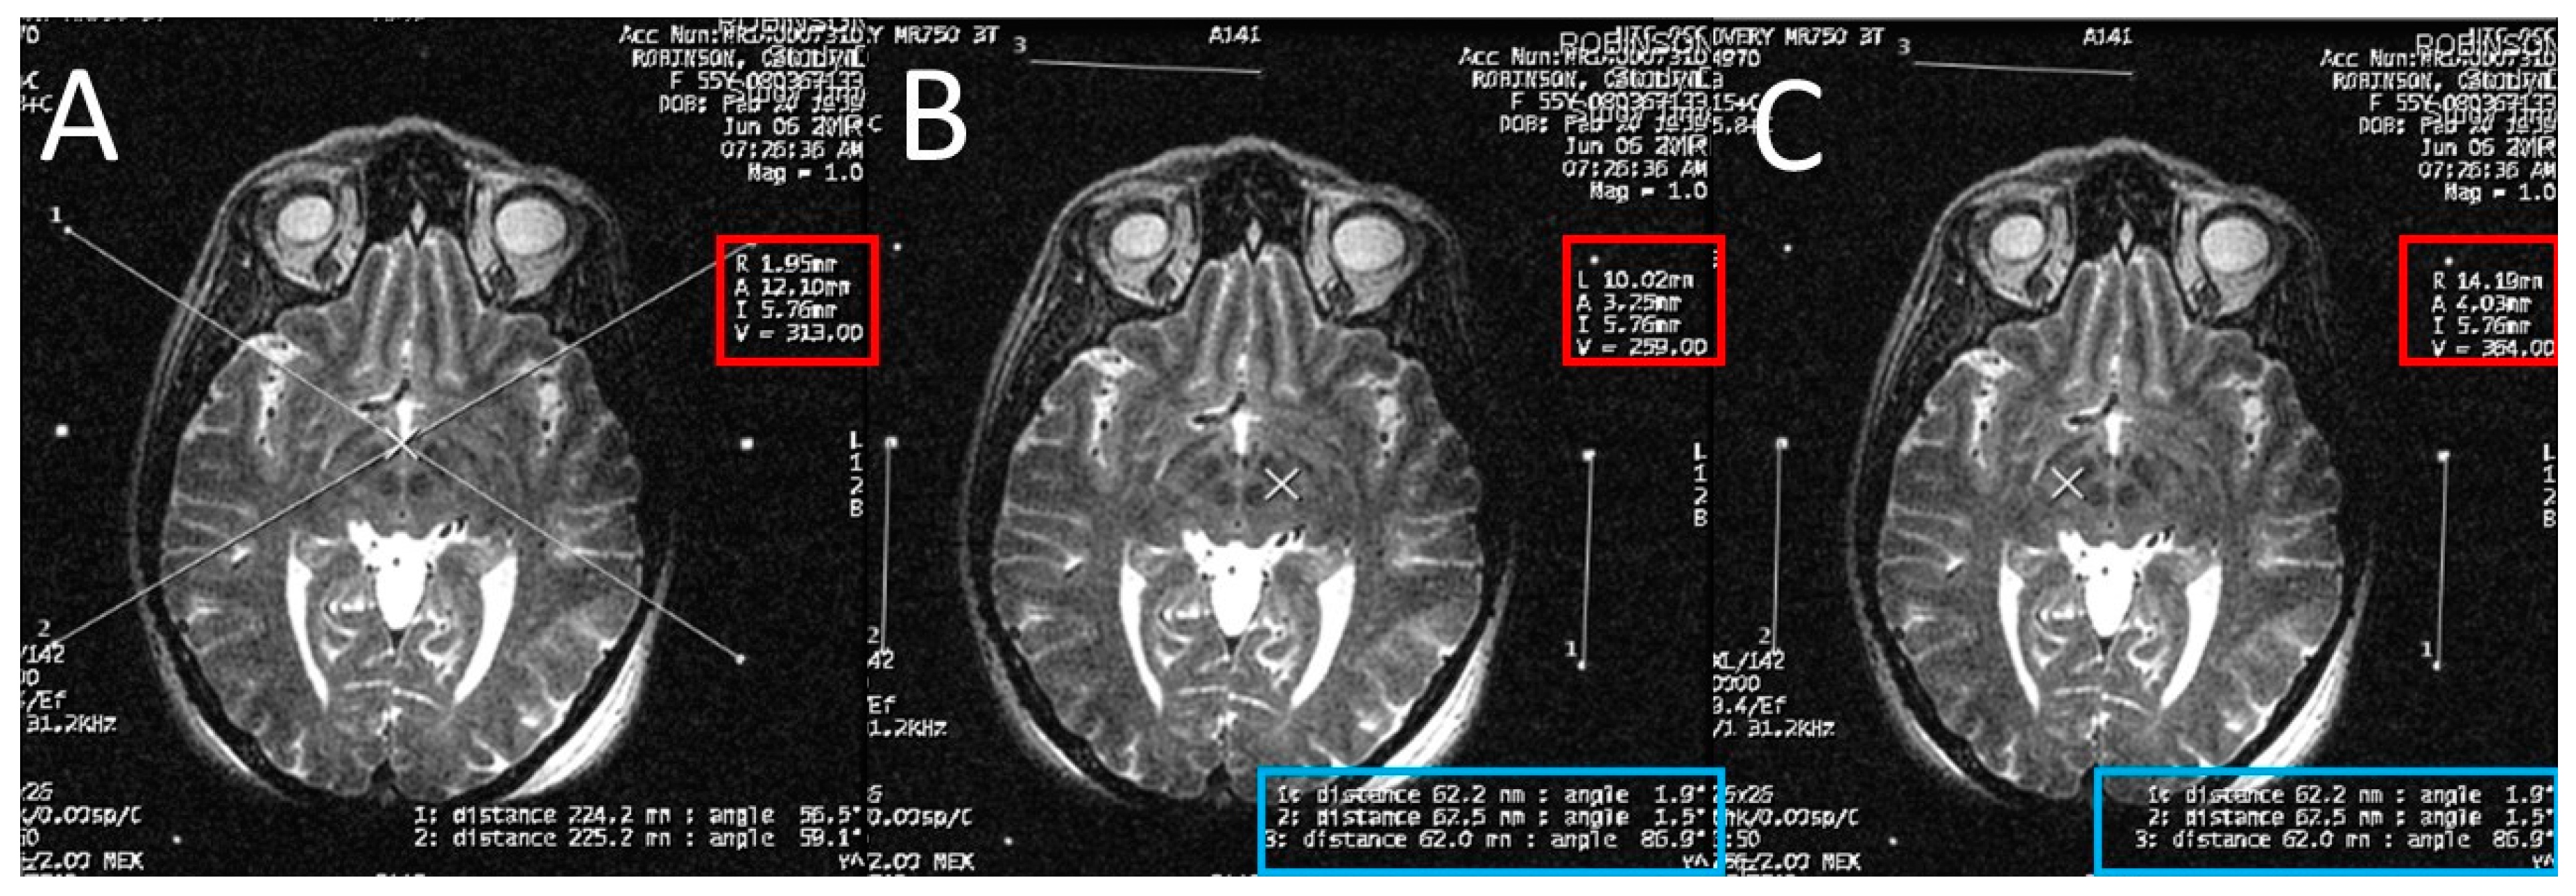

The STN is the hypointense structure located lateral and anterior to the red nucleus on axial T2 MRI (Figure 4) [8]. The center of the STN hypointensity was identified at the extension of a straight line drawn at the anterior margin of the RN bisecting the STN. Then, the coordinates were calculated using the same Excel worksheet.

Figure 4.

Calculating the subthalamic nucleus (STN) coordinates from the magnetic resonance imaging (MRI) console. (A) two diagonal lines intersecting at the center of the frame at the STN level with MRI coordinates of the center of the frame shown inside the red square; (B) a crosshair at the center of the left STN, with its MRI coordinates shown inside the red square, two line are drawn between the middle and lower fiducials on both sides of the frame and their lengths (in the blue rectangle) are used to calculate the Z coordinate; (C) a crosshair at the center of the right STN, with its MRI coordinates shown inside the red square, two line are drawn between the middle and lower fiducials on both sides of the frame and their lengths (in the blue rectangle) are used to calculate the Z coordinate.